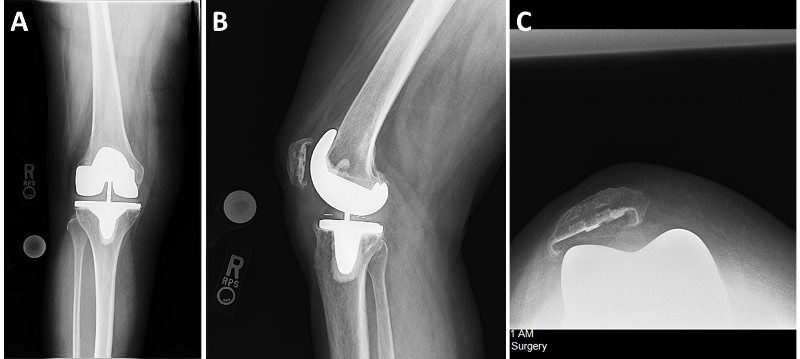

Radiographic examination (Figure 1A-C) showed well-fixed and well-aligned implants, with slight lateral patellar tilt on the merchant view. The posterior condylar offset appeared appropriate, and the implants did not appear oversized.

Fig. 1